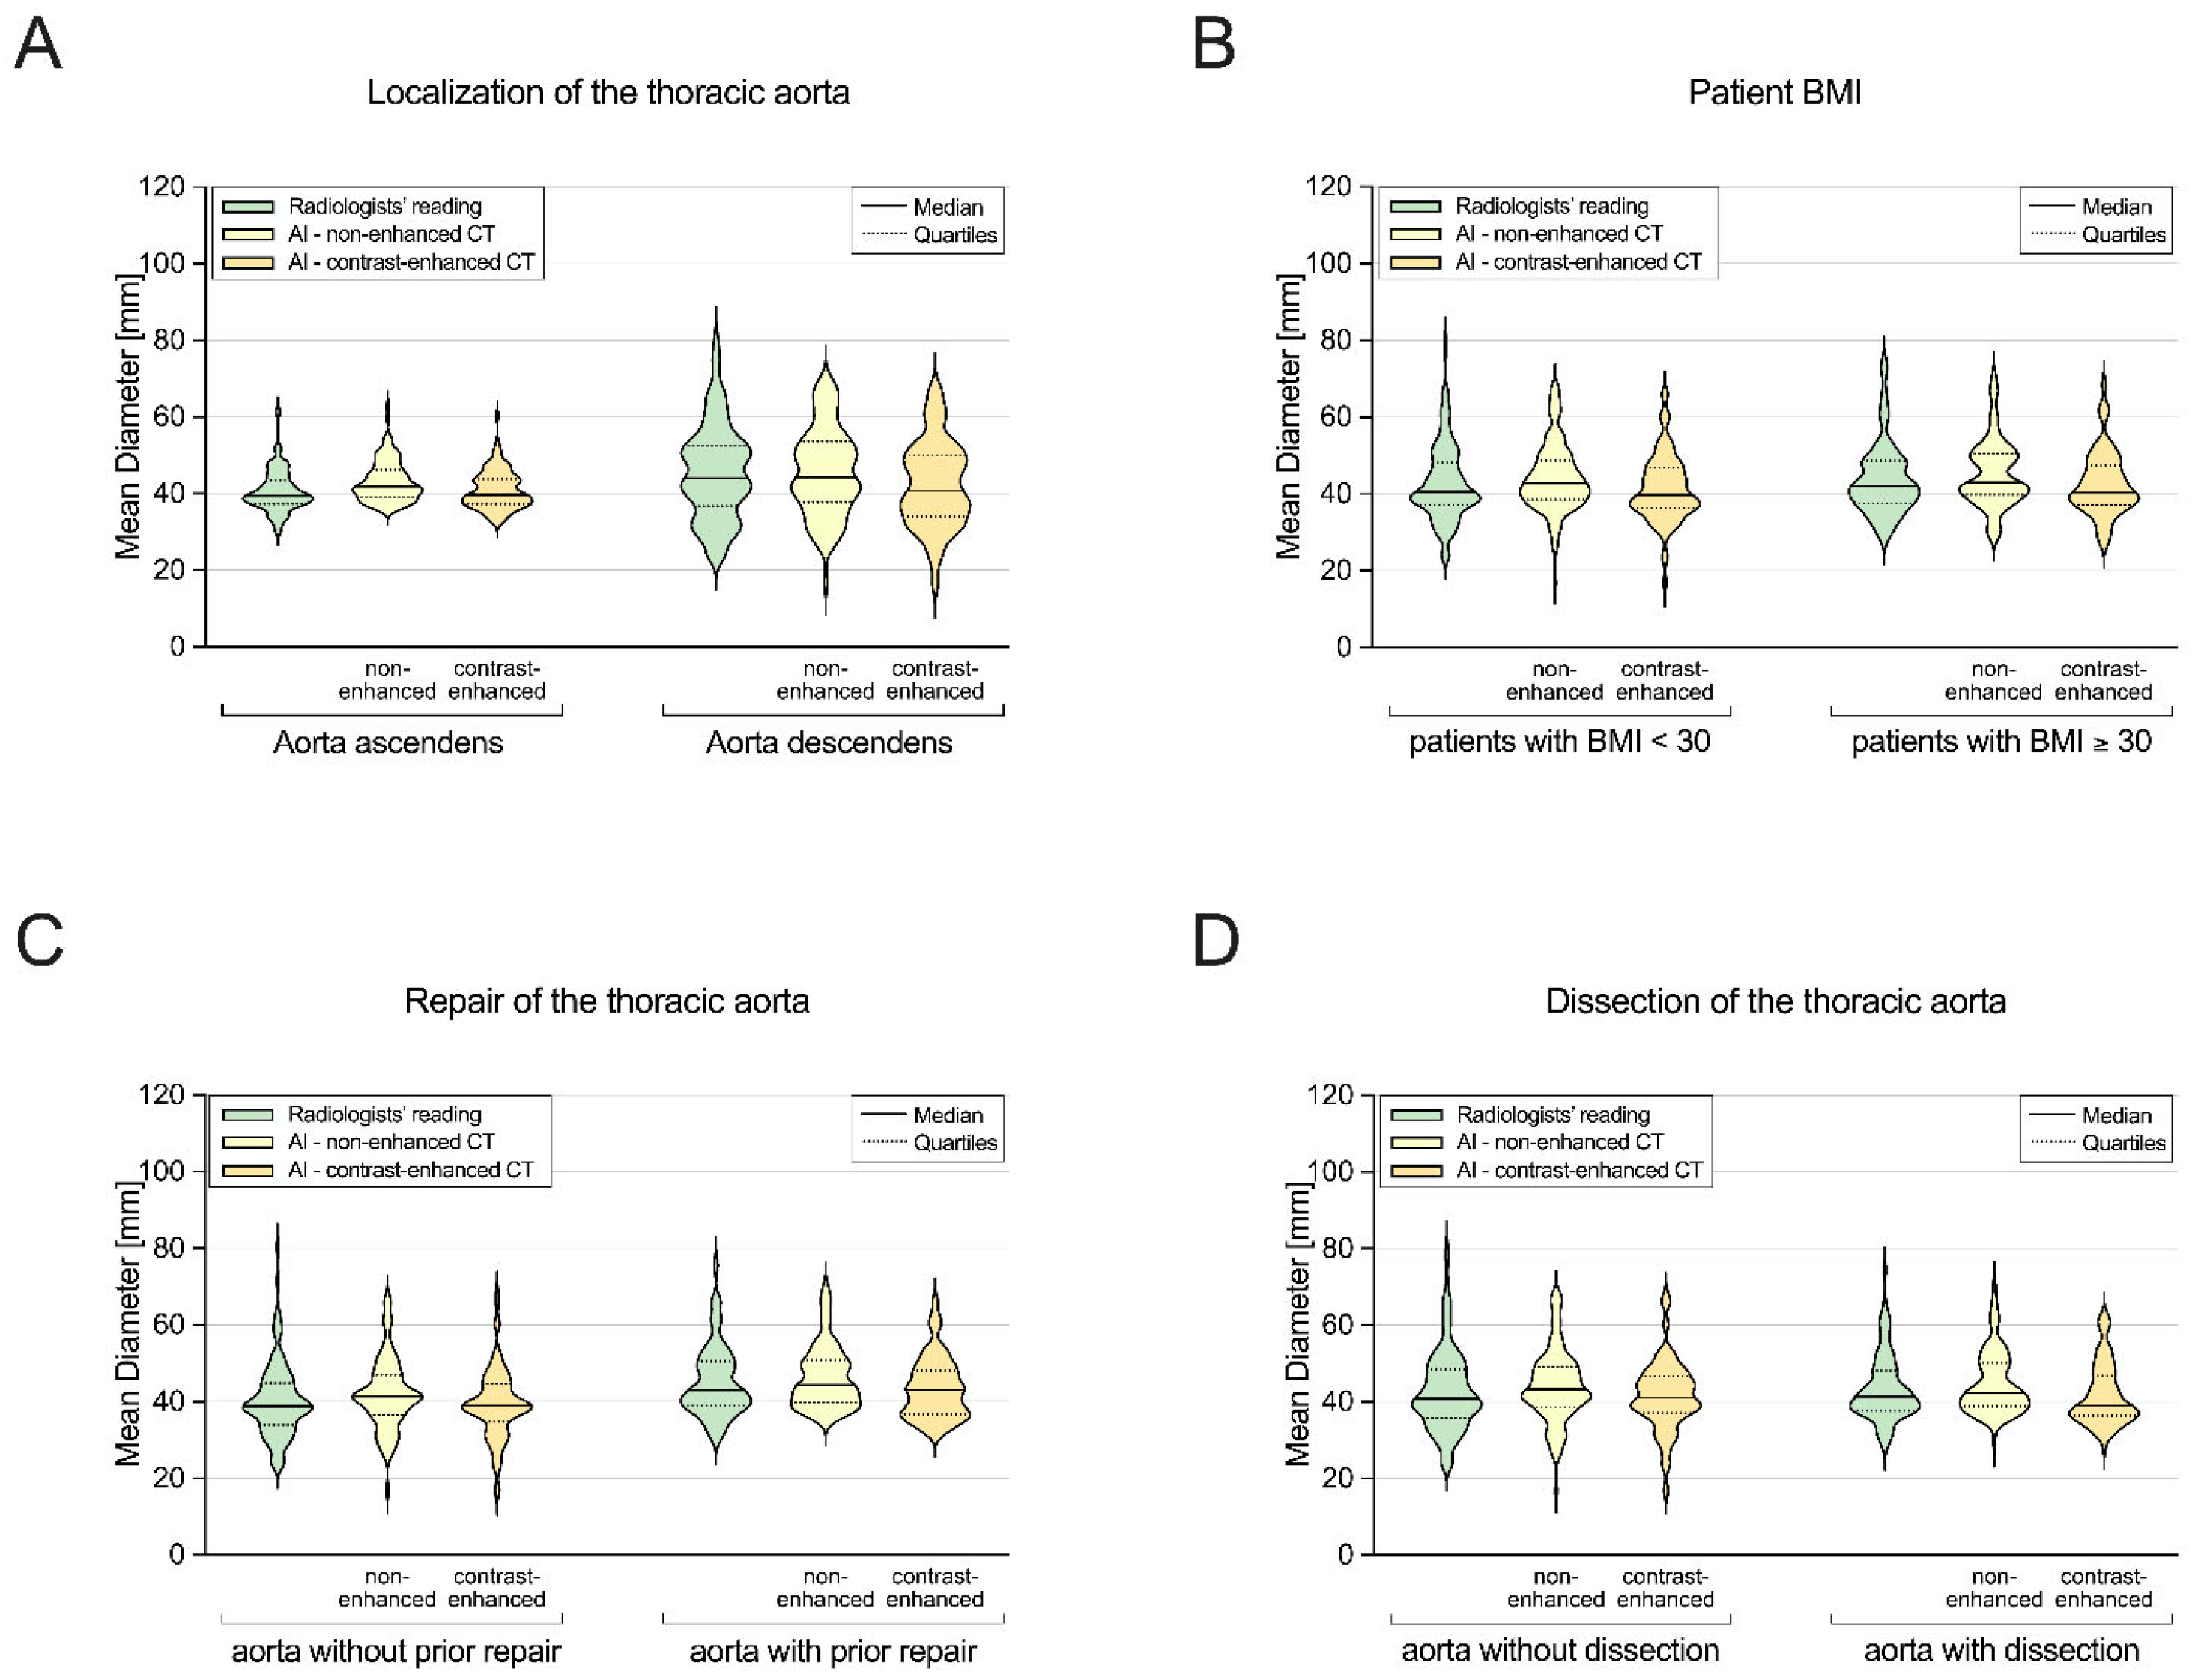

3.3. Subgroup I: Ascending Aorta vs. Descending Aorta

3.4. Subgroup II: Non-Obese vs. Obese Patients

3.5. Subgroup III: Patients without vs. with Prior Aortic Repair

3.6. Subgroup IV: Patients without vs. with Aortic Dissection